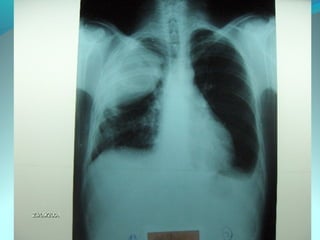

Image radiologique bilaterale

A droite : clarté sous claviculaire et axilaire droite arrondie de 3 cm de

diam entourée d une paroi de 4mm d’épaisseur

Le 1/3 sup du poumon droit est le siege d’opacité nodulaire avec

quelque clarté

A gauche: le 1/3 moyen est le siege d’opacité nodulaire et de clarté de

taille variable

DIAGNOSTIC:

Tuberculose pulmonaire bilaterale cavitaire